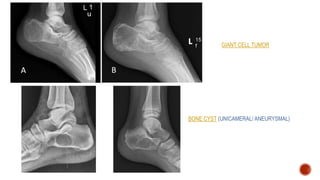

GIANT CELL TUMOR

BONE CYST (UNICAMERAL/ ANEURYSMAL)